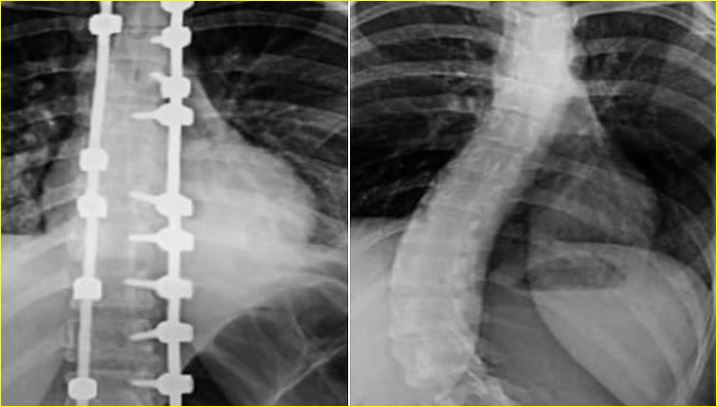

وأضاف أن العملية استغرقت خمس ساعات، وأُجريت تحت المراقبة العصبية الدقيقة، وشملت تصحيح العمود الفقري على امتداد 12 فقرة باستخدام أحدث أنظمة التثبيت الجراحي، مع إغلاق تجميلي متقدم للجرح وتقنيات لإعادة توازن الكتفين وتناسق الخصر. وأكد أن نجاح العملية تحقق بفضل توفر أحدث الأجهزة الطبية وكوادر طبية وتمريضية عالية التأهيل.